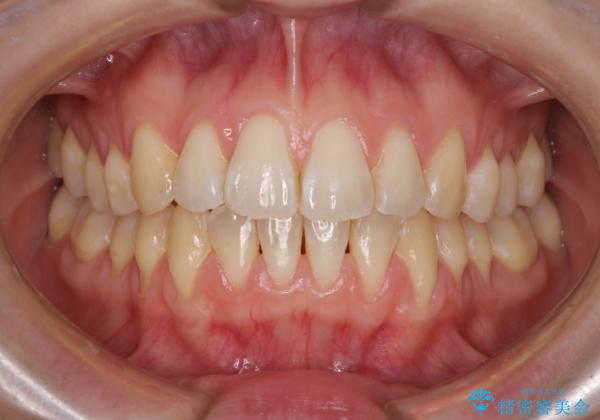

気になるデコボコとオープンバイト インビザラインでの矯正治療

- 前歯のデコボコと上下が開いていることを気にして来院された患者様です。

いわゆるオープンバイトは、インビザラインによる治療が適しているため、インビザラインにて治療を行うこととしました。

オープンバイトは容易に後戻りを起こすため、少しでも後戻りリスクを軽減するために舌癖改善のトレーニングをしっかりと行っていただきました。